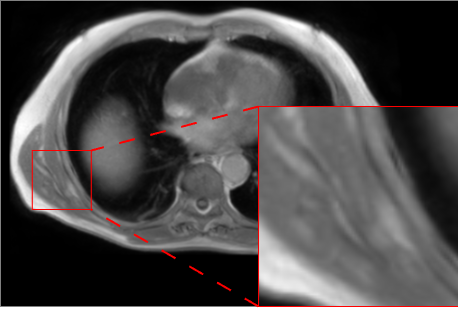

Figure 2 presents qualitative results for the MR-to-CT translation task on the AB dataset. The displayed axial slices include zoomed views on bone structures such as the ribs and right scapula, the latter being among the most challenging to synthesize. Visual inspection reveals that AFP-based models generally produce sharper reconstructions than their L1 counterparts, with nnResU-Net further improving bone delineation compared to nnU-Net. The combination of AFP with nnResU-Net yields particularly accurate results for the scapula, where other models fail to reconstruct the correct morphology.

![]() |

| Input MR | nnU-Net L1 | nnU-Net L1 + AFP |

| Real CT | nnResU-Net L1 | nnResU-Net L1 + AFP |

Quantitative results in Table 3 and Table 4 are computed on the combined AB, HN, and TH datasets (three separate models, with all predictions gathered as in the challenge online validation report). For intensity-based metrics, nnResU-Net with L1 loss achieves the best performance across MAE, PSNR, and MS-SSIM, confirming that the residual design improves robustness and gradient flow compared to the baseline nnU-Net. This is consistent with the fact that L1 loss directly optimizes for MAE and related metrics, whereas AFP is not designed to maximize pixel-wise accuracy. In contrast, segmentation-based results show that AFP consistently outperforms L1, and nnResU-Net surpasses nnU-Net, which aligns with the visual observations of more accurate bone reconstruction and sharper anatomical boundaries in AFP-based outputs.